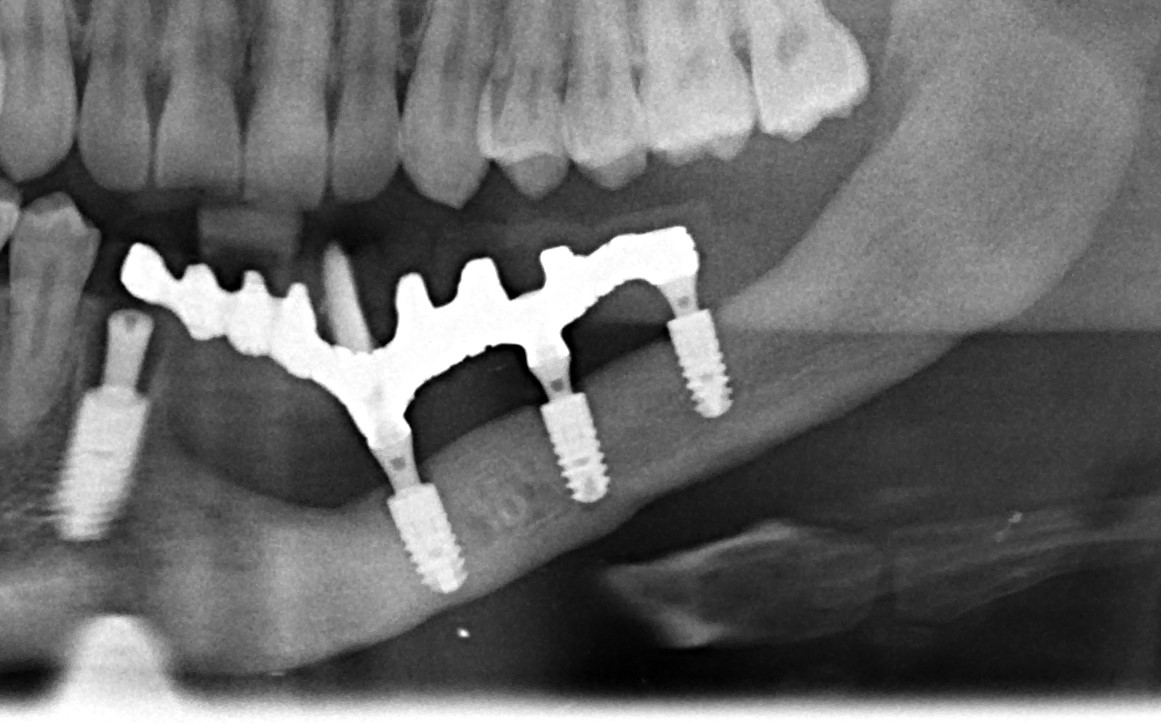

На первое место я бы поставил форму дефекта. Немного забегая вперед (а это будет темой следующей статьи), выбор метода наращивания костной ткани зависит, в основном, от двух параметров: биотипа кости и формы атрофического дефекта. Подробнее об этом я написал здесь>>. В общих чертах, некоторые случаи потери кости настолько сложные для наращивания, что сопоставляя стоимость, целесообразность и возможные риски, лучше отказаться от остеопластики в пользу какой-нибудь методики нетрадиционной сексуальной имплантации, типа «всё на четырёх», ультракоротких или базальных имплантов. Да-да, вы не ослышались! Базальные имплантаты — вполне себе метод, если отобрать их у доктора Иде, если использовать его по показаниям.

Как, например, в этом случае. Правда, это Ankylos: